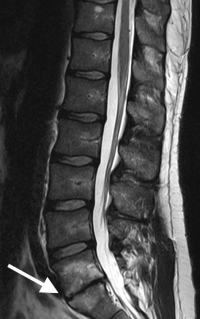

The MRI findings of isolated disc resorption (IDR) are classic. First, the disc will be very narrowed and have lost most of its original height. The disc space will appear black due to the loss of water from the nucleus and then loss of the nucleus itself.

The cortical endplates of the bone, which are normally uniform and regular, are found to be irregular with small endplate fractures. Some call these “moth-eaten” or “rat-bite” appearances.

The inside or internal body of the vertebra will be whitened along these fractured edges (noted on a T2 image in which water is white). This is due to fluid accumulation from the fractured trabecula, which seeps into this area.

(Click to Enlarge Image) Mild Degenerative Disc Disease The arrow points to the L4-5 disc which has lost its white signal. The disc still has good height remaining and the endplates are smooth and intact.